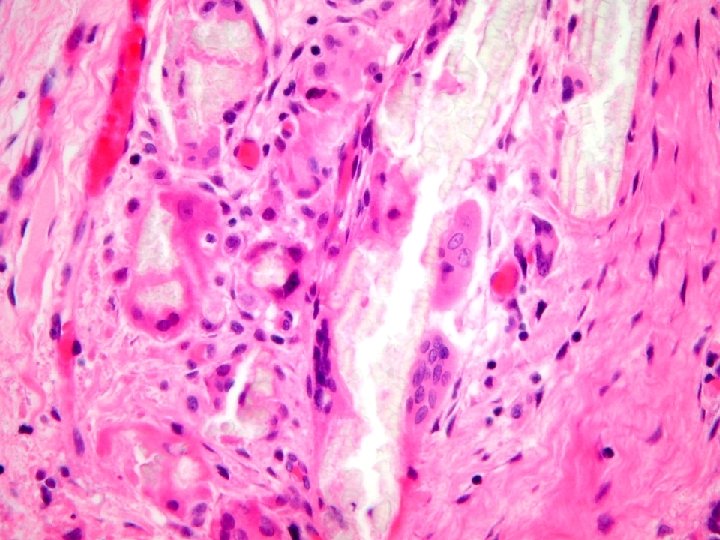

S 00 -45788 Left kidney, fragmentary removal: • End-stage kidney – Chronic tubulointerstitial inflammation and scarring, consistent with obstruction and/or pyelonephritis. – Marked parenchymal crystal deposits, probably secondary oxalate deposition.

« The findings here are probably secondary oxalosis on the basis of chronic renal failure, although I concede that the degree of crystal deposition is exceptional. I should add that there are congenital metabolic errors which usually lead to massive levels of oxalate retention in tissues, but these usually lead to end-stage renal disease before the age of 20. »

Diagnosis Renal Biopsy: • Acute bacterial interstitial nephritis with pus casts probably on the basis of partial ureteral obstruction by calcium oxalate debris. • Tubular deposition of calcific debris, both calcium phosphate and calcium oxalate. • Possible subclinical immune complex glomerulonephritis. • No evidence of rejection. • (G 0 CG 0 I 3 CI 2 T 1 CT 2 V- CV- AH 2 MM 0)

Diagnosis Renal Biopsy: • Chronic pyelonephritis with medullary calcium oxalate deposition related to systemic oxalosis • No evidence of rejection • Banff scores: – G 0 CG 1 I 1 CI 1 T 0 CT 1 V 0 CV 1 AH 0 MM 0